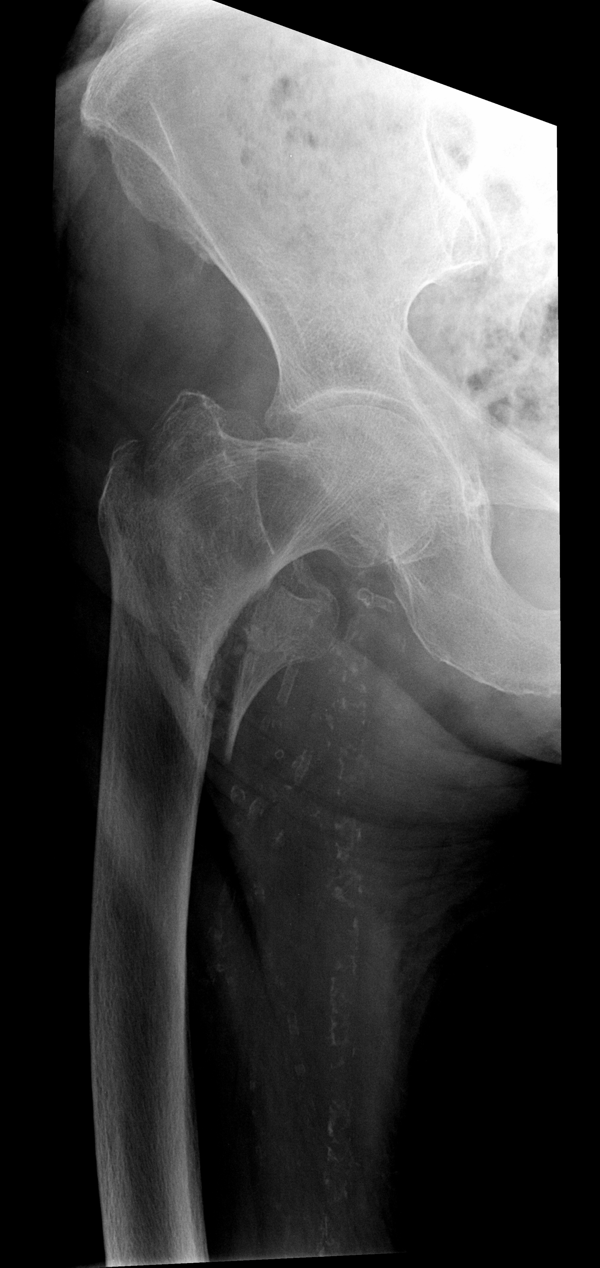

Перелом шейки бедренной кости.

Решающее значение в установлении диагноза перелома шейки бедра имеет рентгенография тазобедренного сустава. У пожилых пациентов приведенные выше симптомы могут проявляться нечетко, а такие заболевания как инсульт или невропатия, вообще, не позволят поставить правильный диагноз без рентгена. Где сделать рентген? Перелом шейки бедра всегда сопровождается сильной болью, поэтому любые лишние движения оборачиваются новыми мучениями, а сопутствующие заболевания внутренних органов усугубляют ситуацию! Решение есть - воспользоваться уникальной услугой – цифровой рентген на дому. К вам приедет врач рентгенолог-травматолог, который выполнит весь комплекс лечебно-диагностических мероприятий и подробно расскажет, что делать дальше.

Получение качественных рентгеновских снимков на дому предъявляет серьёзные требования к рентгеновской аппаратуре. Далеко не каждый переносной рентгенаппарат позволяет получать снимки необходимого качества, чтобы достоверно поставить диагноз. Используемый нами рентгенаппарат АРА 110/160 в комплексе с компьютерным радиографом позволяет получать цифровые рентгеновские снимки высокого качества у пациентов различной комплекции и является уникальной услугой в Санкт-Петербурге, предоставляемой на дому.